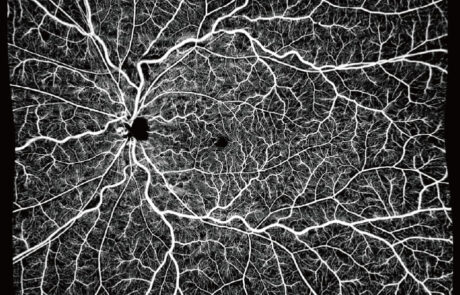

400KHz Ultra-Widefield

Full-Range SS-OCTA

Das TowardPi OCT-System ist das weltweit erste 400-kHz-Ultraweitwinkel-Vollbereichs-SS-OCTA mit vollständig eigenentwickelten Kernkomponenten.

Es ermöglicht eine 120°-Ultraweitwinkel Aufnahme in nur 7–15 Sekunden und liefert hochauflösende Bilddaten bei maximaler Effizienz.

Integrierte KI-Algorithmen unterstützen präzise Segmentierung, choroidale OCTA-Analysen sowie umfassende Fluss- und Strukturmessungen. Exklusive Funktionen wie OCTA des vorderen Augenabschnitts, iSpot-Analyse und Gefäßdichtebewertung eröffnen neue diagnostische Möglichkeiten im modernen Krankheitsmanagement.

Klinische Bilder